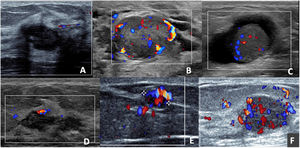

When analysing the AMEs with colour Doppler, the vast majority (11 of 13) presented discharge, the type of vascularisation was internal and peripheral (8 of 11) and with multiple pedicles (7 of 11) (Fig. 2), which led to a preference for biopsy versus short-term follow-up.

Adenomyoepitheliomas in colour Doppler mode. A) Oval, hypoechoic, circumscribed and non-vascularised nodule. B) Oval, hypoechoic, circumscribed nodule, presenting perinodular and intranodular vascularisation. C) Solid-cystic, oval nodule with intranodular vascularisation in the solid portion. D) Nodule with exclusively capsular vascularisation. E) Oval nodule, with marked vascularisation; the presence of a single pedicle leading to the nodule can be observed. F) Oval, hypoechoic nodule, with marked nodular and capsular vascularisation with the presence of multiple tortuous pedicles entering the nodule.

On ultrasound, benign AMEs usually manifest as hypoechoic, circumscribed nodules that may have posterior enhancement, whereas malignant AMEs may appear with non-circumscribed margins and posterior acoustic shadow.7 However, it is not uncommon for benign lesions to look suspicious on ultrasound. In this series of cases, most of the lesions were categorised as BI-RADS 4, but no distinctive characteristics were identified between benign and atypical or malignant AMEs (Fig. 4).

In the scientific literature, the type of vascularisation of these lesions has not been systematically described. However, in our series, the role of colour Doppler is important, which facilitated better characterisation of the nodules, since 11 of 13 exhibited discharge and in the vast majority (8 of 11), the vessels were visible both in the periphery and within the lesion and with multiple pedicles (7 of 11) (Fig. 2). These findings differ from the Young Mi Park series, where most of the nodules only exhibited peripheral vascularisation.8 A study by Gkali et al. highlights the role of elastography in the diagnosis of AME of the breast.9 Elastography values were not included in our study, as they were not used routinely at our centre.